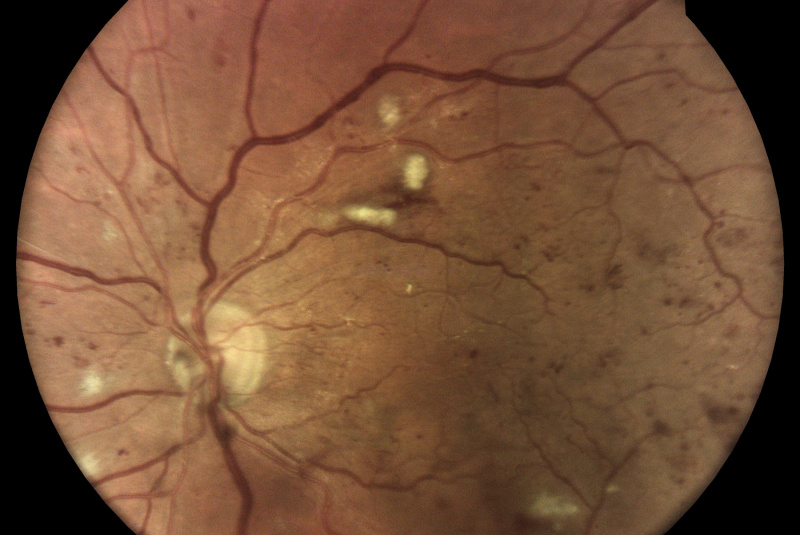

Diabetická retinopatia

Diabetická retinopatia je hlavnou príčinou straty zraku u dospelých vo veku medzi 20 - 74 rokov. Viac ako jedna tretina z odhadovaných 285 mil. ľudí s cukrovkou na celom svete vykazuje príznaky diabetickej retinopatie. Diabetická retinopatia je na vzostupe v dôsledku zvyšujúcej sa prevalancie cukrovky, stárnutia populácie a predlžujúcej sa dĺžky života ľudí s cukrovkou.

- infračervené mapy zvýrazňujúce svetlé a červené lézie/poškodenia